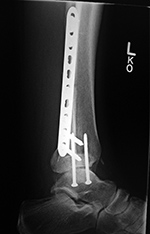

change in position (Ruedi, 2007; Benjamin, 1994; Hunter, 2001). A screw that is used to stabilize the distal tibiofibular

syndesmosis is called a syndesmotic screw.

This screw is placed across the distal tibiofibular

joint parallel and 1–2 cm proximal to the joint

line. One or more syndesmotic screws can also be placed

through the holes of a fibular fixation plate (figure: syndesmotic screws; figure: syndesmotic screws and medial malleolus cortical screws).

Syndesmotic screws are usually removed 6 –12

weeks after placement, after the interosseous

membrane has healed (Ruedi, 2007; Benjamin, 1994; Berquist, 1995; Freiberg, 2001; Hunter, 2001).